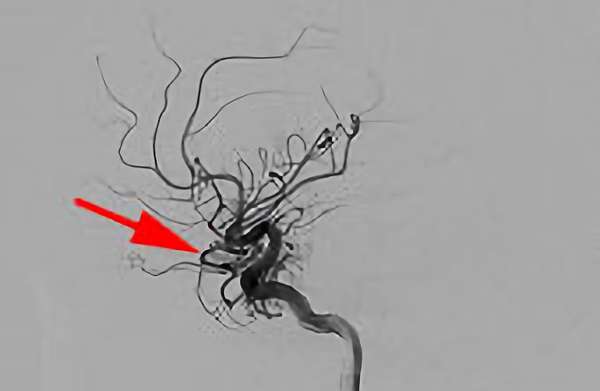

No.1585 手術前

No.1585 手術中

No.1585 手術後